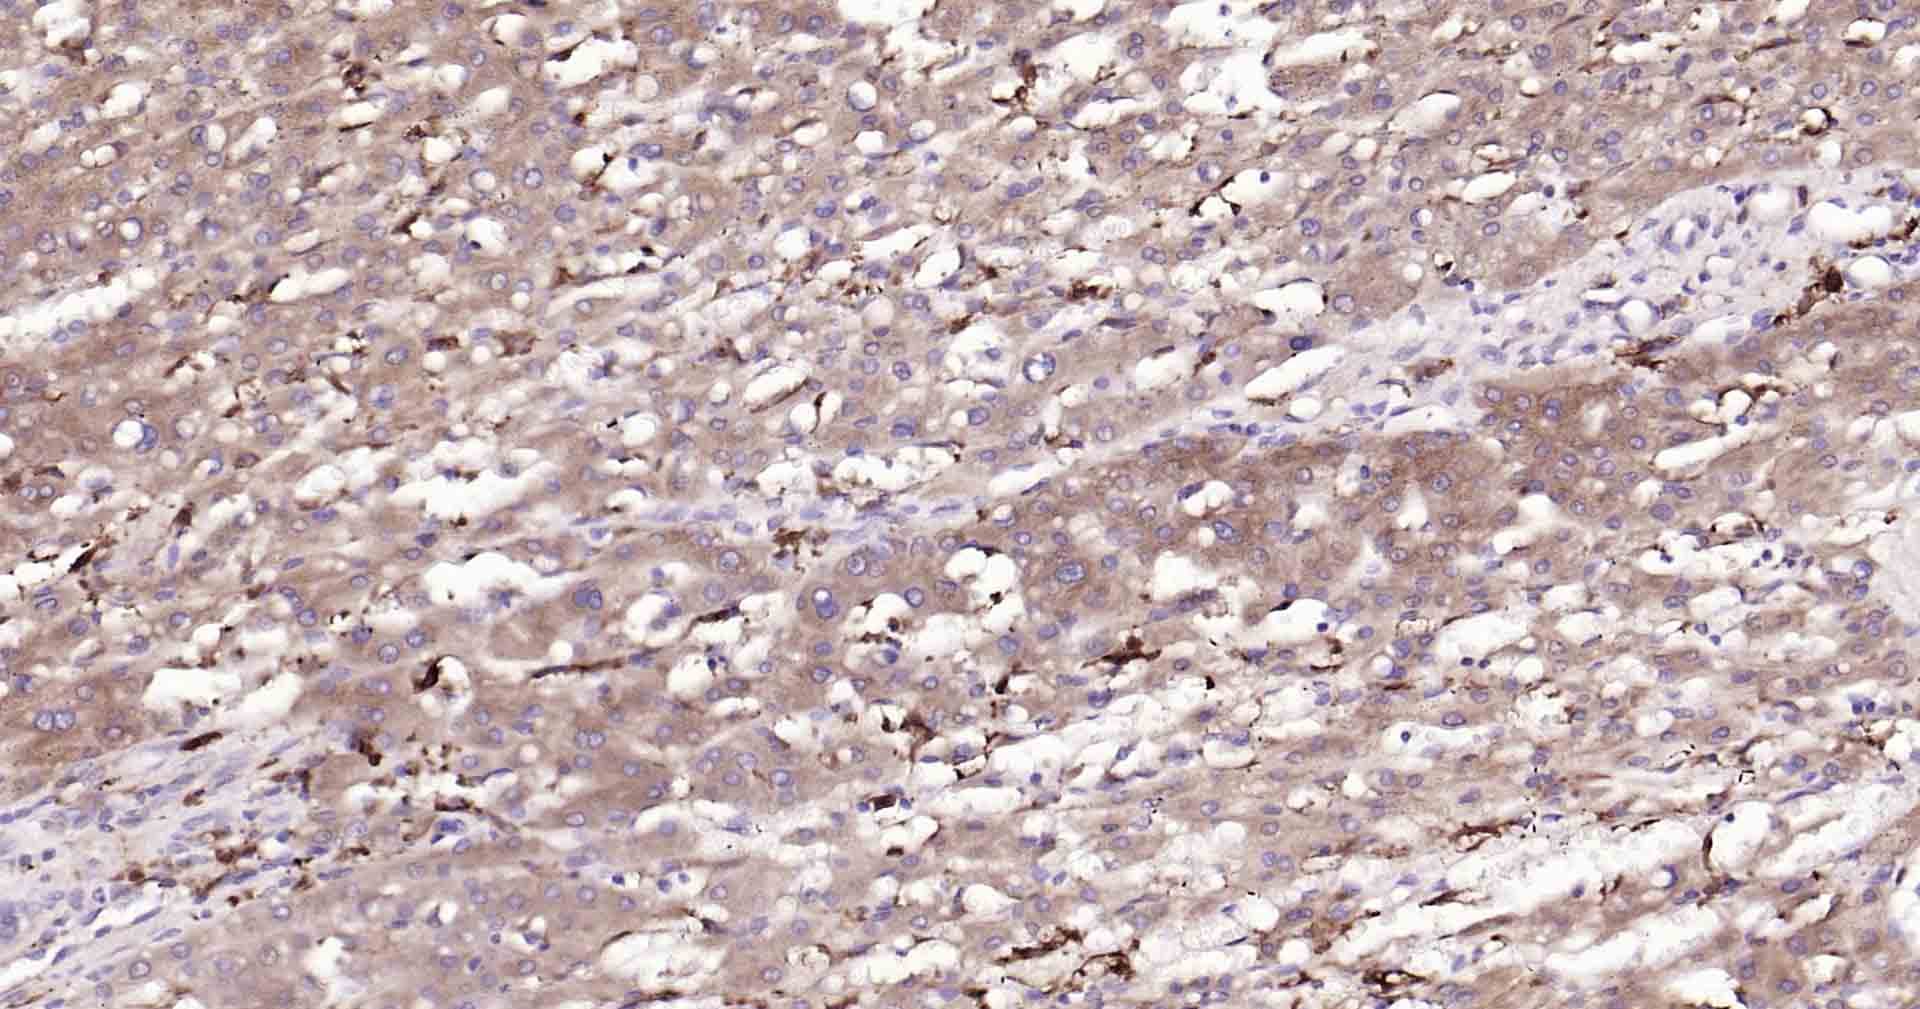

Paraformaldehyde-fixed, paraffin embedded Human Liver Cancer; Antigen retrieval by boiling in sodium citrate buffer (pH6.0) for 15 min; Antibody incubation with Beclin 1 Monoclonal Antibody, Unconjugated(bsm-41365R) at 1:50 overnight at 4°C, followed by conjugation to the SP Kit (Rabbit, SP-0023) and DAB (C-0010) staining.